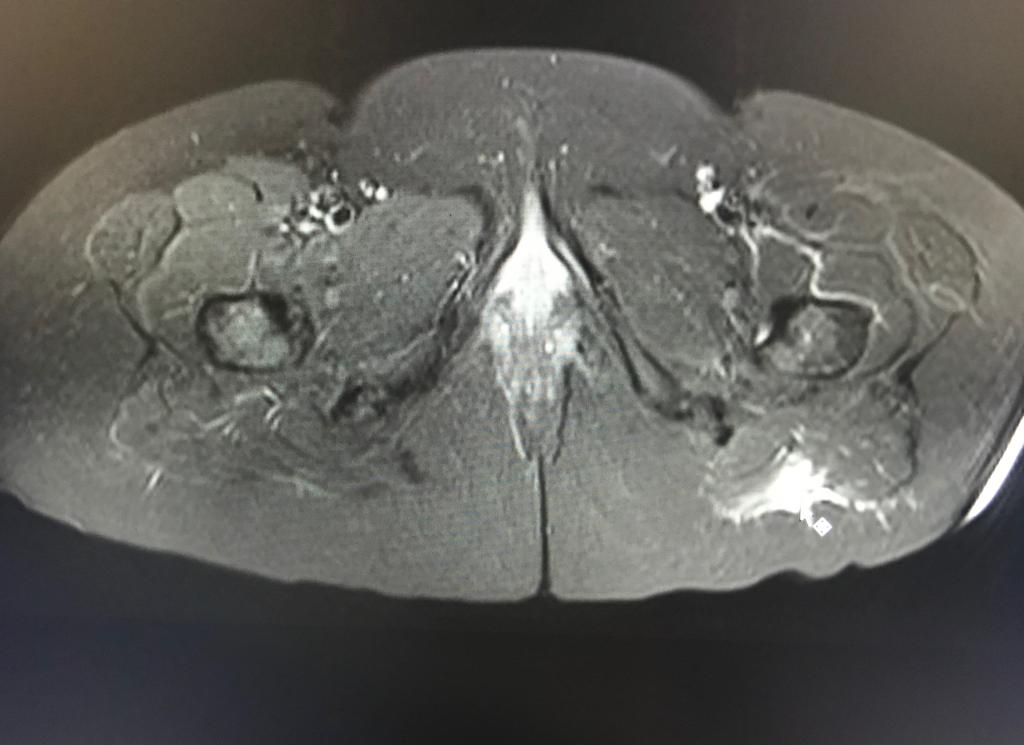

La RM es esencial para el diagnóstico de la topografía, severidad y extensión de los desgarros musculares.

Un compromiso fibrilar mayor del 15% del área muscular con una longitud superior a los 13cm y una localización central al vientre muscular , presenta un peor pronóstico y mayor tiempo de rehabilitación.

Un diagnóstico temprano es fundamental para evitar la retracción muscular y la formación de tejido cicatrízal.